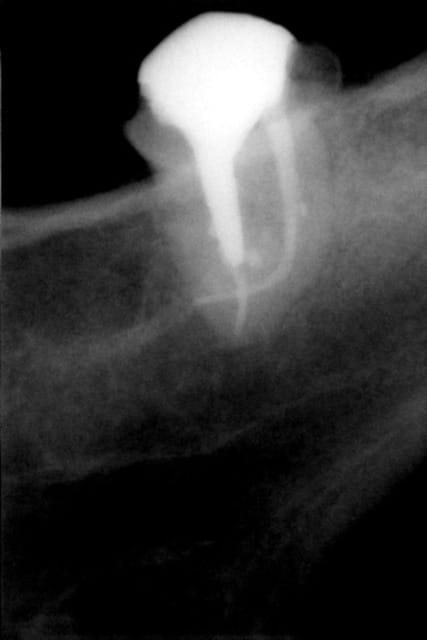

thermafil sans le laser à l'époque , cela marche aussi !

Thermafil t0zch4 - Eugenol